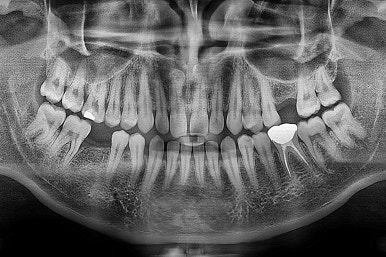

왼쪽이 치료 전, 오른쪽이 연산동임플란트 치료 후 X-ray 사진입니다.

전후 사진을 비교해 볼게요.

비교적 짧은 시간 안에 환자분이 만족하는 치료를 할 수 있었어요.

이상 어금니 결손 부위의 연산동임플란트, 틈새 부위의 치아교정치료 및 충치치료가 한 곳에서 가능한 키다리아저씨치과의 치료사례였습니다.